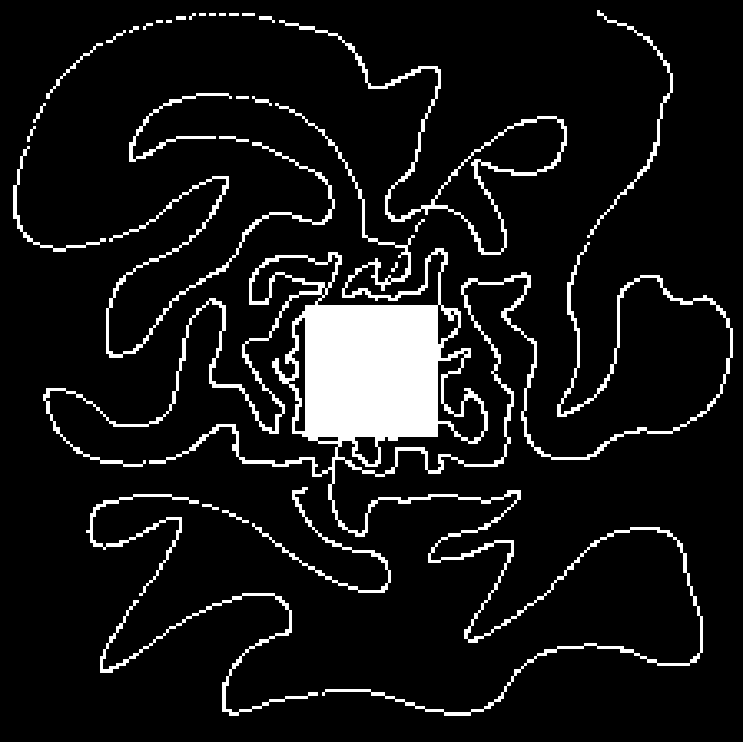

Compressed Sensing (CS) provides a theoretical framework to justify the downsampling of -space (2D or 3D Fourier domain) in Magnetic Resonance Imaging (MRI). CS-MRI is usually based on independent random drawing of -space locations according to a prescribed density. From recent theoretical works [3, 4], one can derive an optimal sampling density that reduces at most the number of samples collected in MRI without degrading the image quality at the reconstruction step [5, 6]. In [7], simulations show that distributions with radial decay (see Fig. 1(a)) with full -space center acquisition perform better in numerical experiments.

However, such sampling schemes are not performed along continuous lines and thus not physically plausible in MRI because of the constraints involved on the magnetic field gradient (magnitude and slew-rate). In [8], we have proposed a new approach to design continuous sampling trajectories based on the solution of Travelling Salesman Problem (TSP), as illustrated in Fig. 1(b). The specificity of this approach is that the empirical distribution of the trajectory can approximate any prescribed distribution . Such a curve is called a -Variable Density Sampler (-VDS). Unfortunately, continuity of the sampling trajectory is not a sufficient condition in MRI and it is not clear how to design admissible gradient waveforms to traverse such a trajectory.